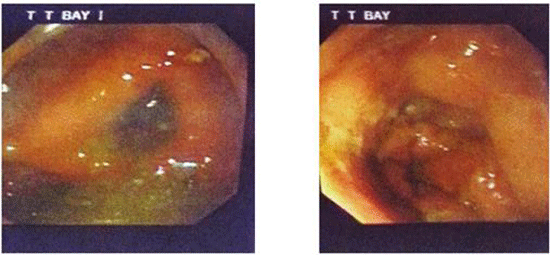

-Nội soi đại tràng cho thấy hình ảnh toàn bộ đại tràng ngang thâm nhiễm, viêm-loét trợt và hẹp lòng, sinh thiết sang thương làm giải phẩu bệnh (Hình 3).

Hình 3. Hình ảnh tổn thương đại tràng ngang trên nội soi đại-trực tràng